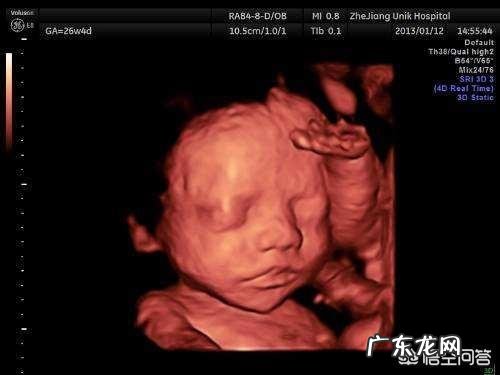

1.相貌有差别的情况 。四维拍照时,胎儿才6个月,还有4个月胎儿才到预产期 。

在这4个月内,胎儿的眼睛,嘴巴,鼻子,头发等等还会进一步发育,所以宝宝出生后的相貌会跟四维照片差别很大 。

因此,四维照片宝宝鼻子嘴巴很大,妈妈也不用太过担心,宝宝还会继续发育的 。